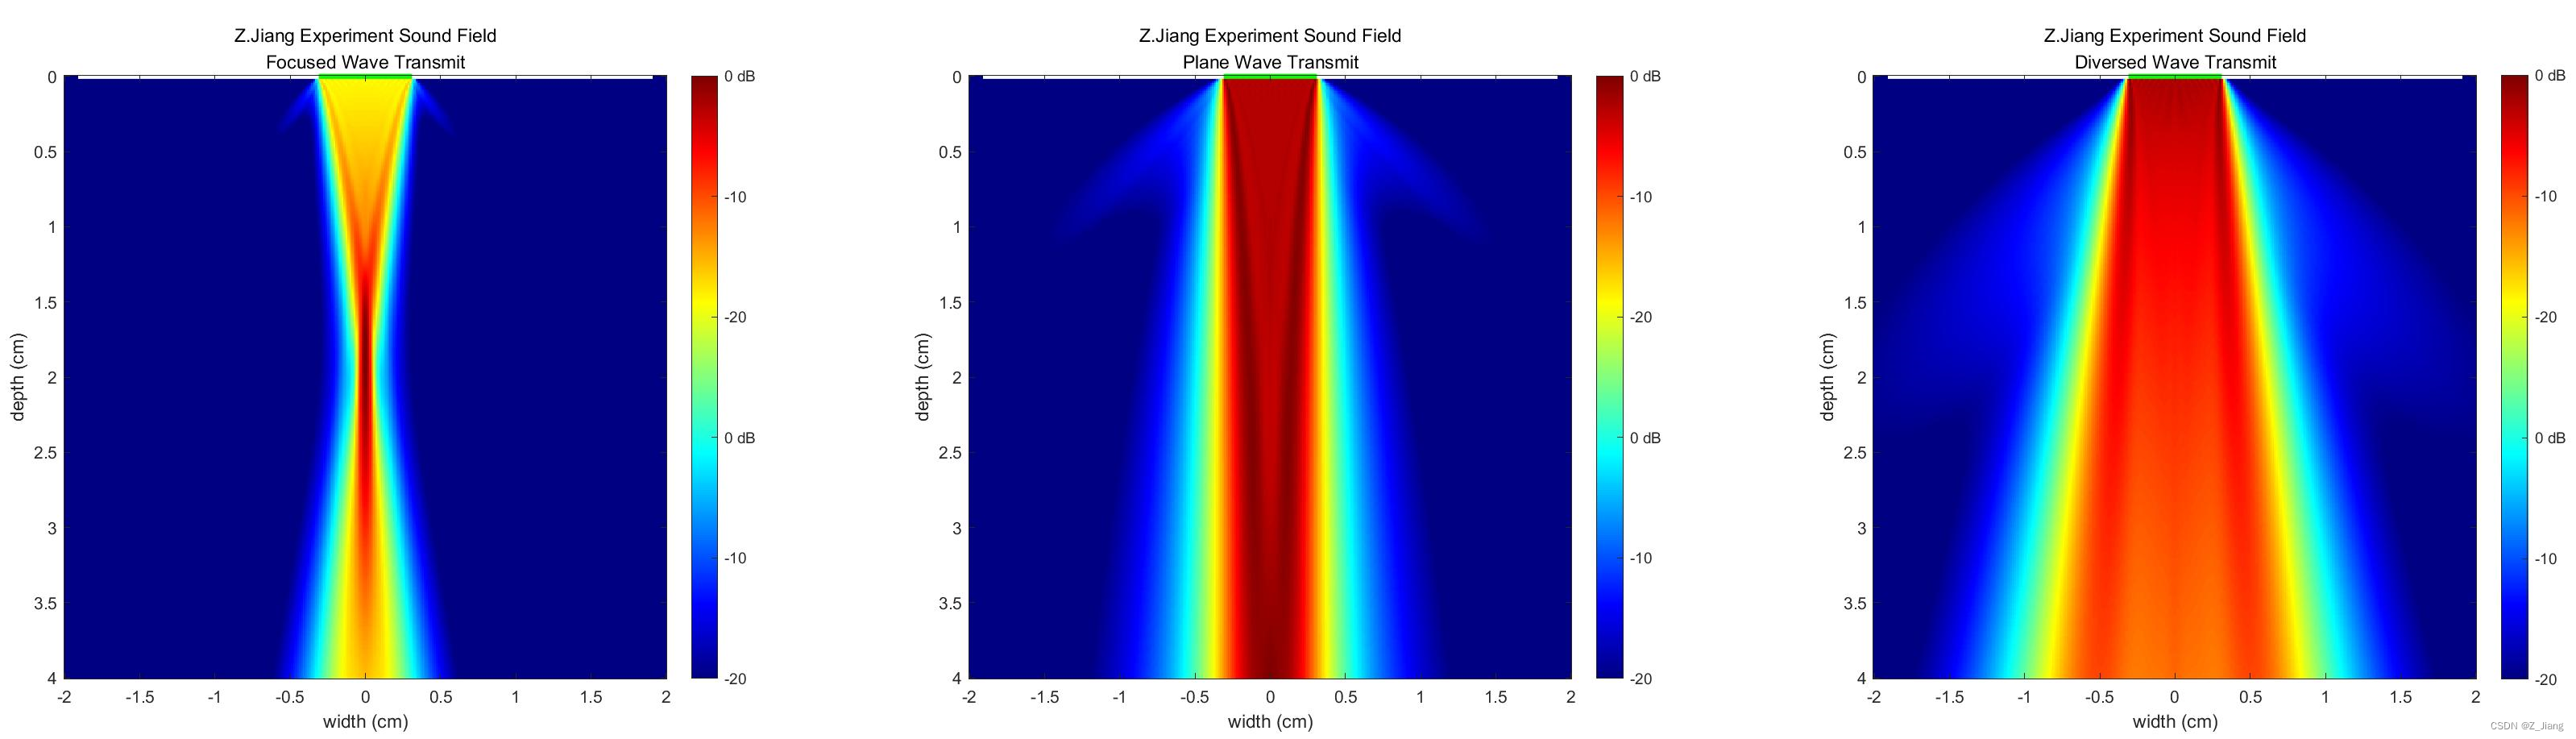

目前为止我们的发射都是聚焦在FOV(Field of View)内,实际上我们的发射聚焦至少可以有三种以上:

1. 焦点在FOV内:聚焦波(Focused Wave)

2. 焦点在无穷远(即无焦点):平面波(Plane Wave)

3. 焦点在探头后面:发射波(Diversed Wave)

4. 其它

我在相同的探头,相同的孔径,用相同的激励波形,以不同聚焦方式,仿真对比一下相同的FOV下的声场,如下图

几种发射,用在成像上各有不同的特性。我先暂时用聚焦波为大家说明,因为目前仍有很多产品使用聚焦波,稍后在波束合成时,再用平面波与发散波进行一下对比分析。